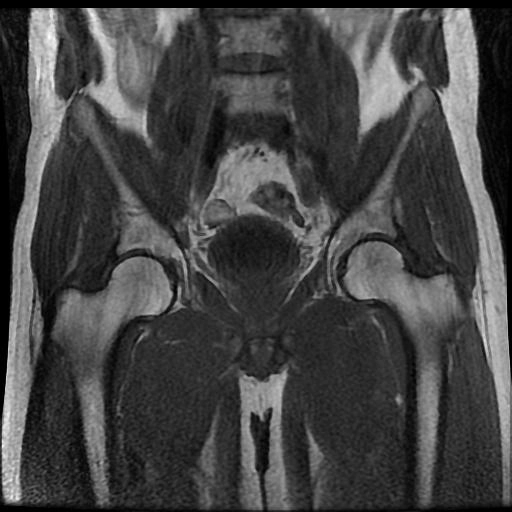

Hoại tử vô mạch chỏm xương đùi (Osteonecrosis of the femoral head)